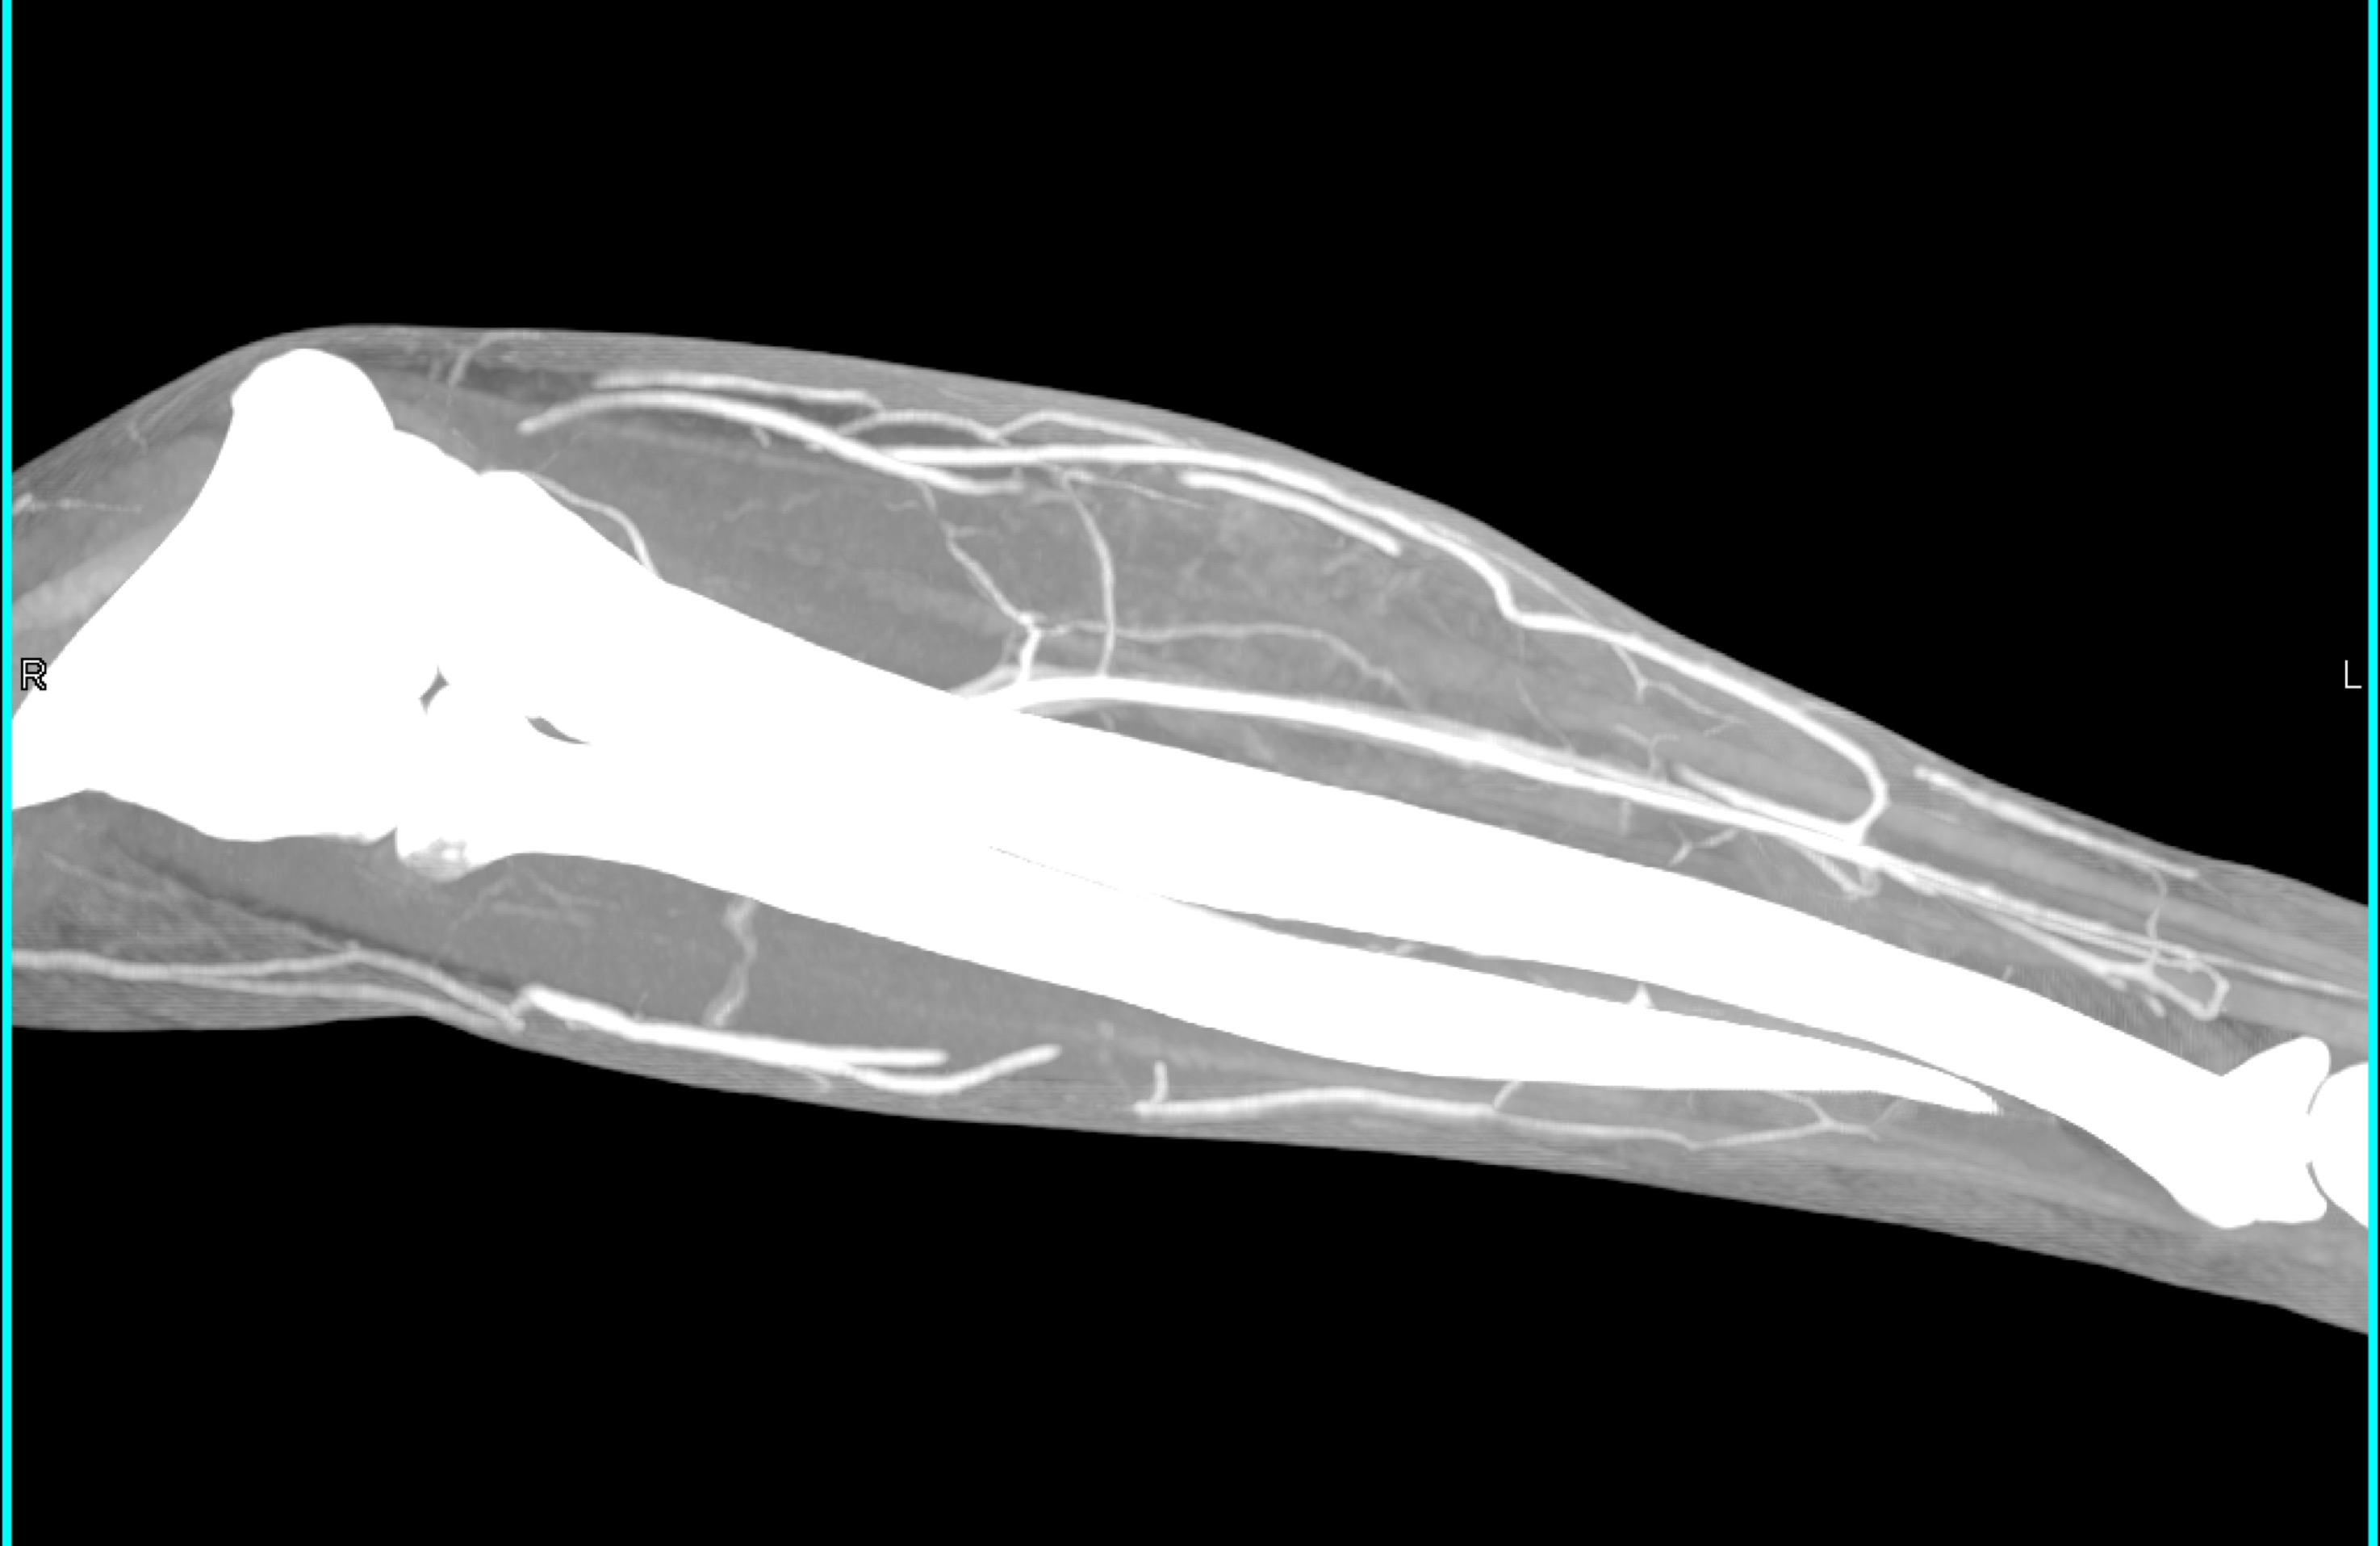

2) In this patient on dialysis for ESRD the best diagnosis is?

normal bypass graft

AV fistulae with aneurysms

vasculitis

infectious vascular disease